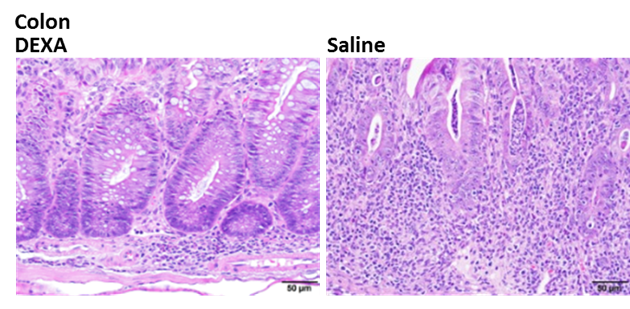

移植帶有冷光的 T 細胞到免疫缺陷小鼠身上,從第 28 天開始出現下痢和體重明顯減輕的病癥,以活體影像分析觀察到冷光的強度隨著發病時間而增加,第 35 天組織病理分析結果發現腸黏膜層發炎浸潤現象。若在 T 細胞移植後第 15 天,給予皮質類固醇藥物,可緩解發炎病癥、且腸黏膜層發炎浸潤現象明顯改善。本試驗服務於第 15 天開始給予藥物後,利用活體影像技術,評估腸道炎症病程,於第 35 天進行腸道組織病理分析、免疫細胞分析、發炎指標測定等技術,評估新藥成效。

移植 T 細胞到小鼠後第 35 天進行腸道組織病理分析,觀察到大腸黏膜層有發炎浸潤現象,若給予皮質類固醇藥物,則可明顯改善病癥。